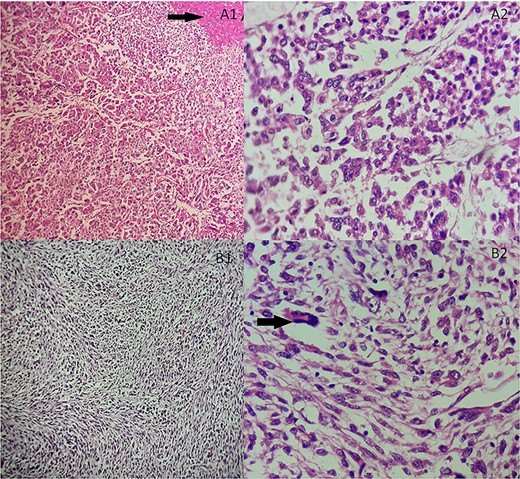

She underwent an adrenalectomy. On gross, the specimen weighed 660 g and measured 12 × 9 × 7 cm. It was well circumscribed, firm, beige-colored, with extensive hemorrhage and necrosis at sectioning; completely effacing the adrenal gland. Hematoxylin–eosin stained sections revealed diffuse sheets of epithelioid and pleomorphic/spindled cells. The epithelioid component consisted of sheets and nests of polygonal cells with clear and eosinophilic (40%) cytoplasm resembling adrenocortical cells with loss of lobulation (Fig. 2A). There was marked nuclear atypia (Nuclear grade III) with high mitotic activity (5/10 high-power fields [HPF]). The pleomorphic component (40% of tumor) consisted of fascicles of spindled and ovoid cells. Nuclei were highly pleomorphic with dense heterogenous chromatin (Fig. 2B). Some multinucleated neoplastic giant cells were identified. The mitotic count was higher (12 mitoses/10 HPF). The Weiss score was 6. On immunohistochemistry, epitheliod cells showed strong, diffuse positivity with Melan-A and synaptophysin. Spindled cells were focally strongly positive for synaptophysin, Melan-A and PS100 (Fig. 3). Immunostains for AE1/AE3, HMB-45, inhibin, desmin, vimentin, caldesmon and SMA were negative in both components. Unfortunately, genetic analysis was not performed, because it is not available in our institution. After a follow-up of 6 months, there was no evidence of local recurrence on CT.

(A) Adrenocortical sarcomatoid carcinoma histological features Carcinomatous component showing sheets and nests of epithelioid cells and necrosis (black arrow). (A1) Hematoxylin and eosin, ×100. (A2) Hematoxylin and eosin, ×400. (B) Adrenocortical sarcomatoid carcinoma histological features: sarcomatous component consisted of spindle-shaped and ovoid cells arranged in fascicular pattern. Associated to some multinucleated neoplastic giant cells (black arrow). (B1) Hematoxylin and eosin, ×200. (B2) Hematoxylin and eosin, ×400.

Adrenocortical carcinosarcoma immunohistochemistry: The carcinomatous areas are synaptophysin positive (A); Melan-A positive (B); PS100 positive (C) and SMA negative (D) (Immunohistochemical stain, ×200).